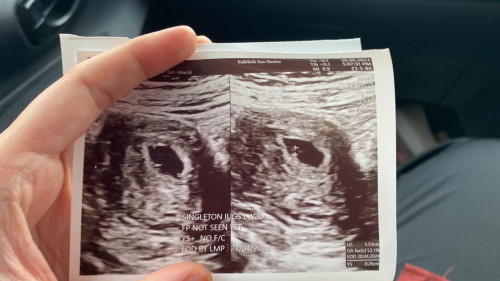

Hi mommiess, saya tgh pregnant 6weeks skrg. Tadi pergi scan tapi nampak kantung besar & yolk sac je kecikk betui. Is that normal 🥺 sbb saya baca banyak yg 6w dah nampak size sikit and siap boleh dgr heartbeat. Tapi saya punya cam kecikkk je, ok ke tuu 🥺🙏🏻 mohon comfortkan saya thank youuu

Alhamdulillah sis sbb da nmpk.. nnti lg 2 minggu g scan blik klu risau ye.. Sis period teratur or x? Mcm sy scan doc scan nmpk mcm sis jgk. Klu ikutkan da 6w tp bila scan dic ukur ckp br 4w5d so lari sikit.. sbb sy period x teratur.. So harini lpas 2minggu lbih sy scan skli lg.. alhamdulillah harini da 8w5d siap pakej dgr jantung.. alhamdulillah sgt2.. So sis jgn stress k.. jaga pemakanan pgerakan.. awal2 ni rehat byk ye.. inshaa Allah moga bby sis membesar dgn jayanya.. inshaa Allah xde pe tu.. 🌸🌸🌸

Baca lagiHi sis, normal saja inshaAllah semua ok. Sy ni 6w dgn 7w pun mmg nampak kantung dan yolk sac. Minggu ke 8 baru sy nampak baby + dengar heartbeat. Jangan terlalu overthinking ya inshaAllah semua ok.

6 weeks ni awal sgt lagi. Mostly pregnant mom 8 minggu pun ada bru nampak kantung.. better kalau nak scan scan ni pergi 12 weeks keatas. As long as pembesaran janin sihat, takyah sedih pon. Jaga diri

Lebih kurang macam saya dulu sis.. week 6 baru ada kantung & yolk sac je sebab baru lagi ni.. nanti lagi 2-3 minggu datang scan.. Semoga dipermudahkan & jaga diri 🥰

awak sama dgn saya scan nmpak yolk sac sahaja. Mnggu depan 8 minggu dr suruh repeat balik scan hehe. Jangan risau normal 6 weeks nmpak yolk sac tu sahaja.

ok la tu 6w dh nmpk cinonet...sy 6w nmpk kantung saja. 9w repeat scan baru nmpk janin dan kedip2.